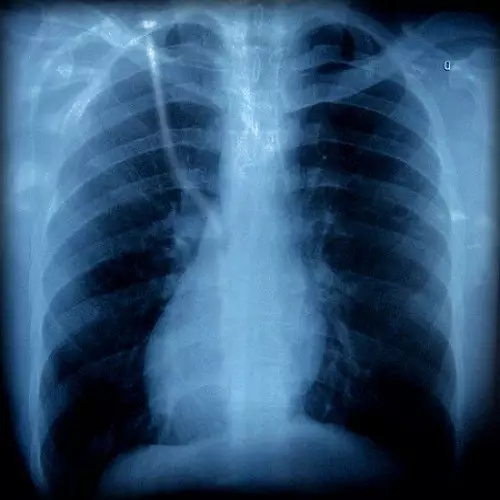

胸片有異

胸外科

咳嗽可以是由肺部腫瘤等疾病引起的,如果胸片或胸部CT上發(fā)現有可疑病變時,應該看看胸外科。一般,呼吸內科大夫也會幫忙轉診的。